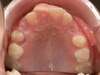

Cas 5 : Description

Absence congénitale des incisives latérales supérieures. Appareils fixes pour créer l’espace nécessaire à la mise en place de facettes en remplacement des latérales.

Après